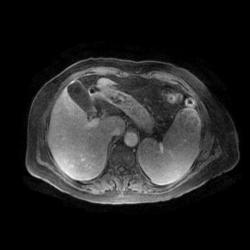

Женщина 47 лет, в течении долгого времени страдала от головных болей. В последние несколько месяцев - прогрессирующая потеря зрения (на оба глаза).

ИП FLAIR Axial

Presented images are corresponded for cerebral (right temporal-occipital region) neoplasia; high grade glioma is most suggested.

Глиальная опухоль.